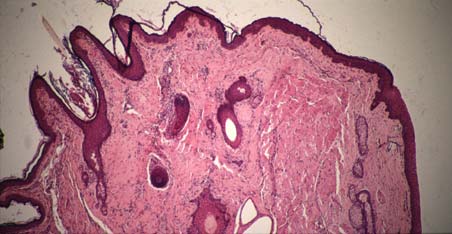

IX-34C Eyelid. Skin with hair (on left), palpebral conjunctiva (on right).